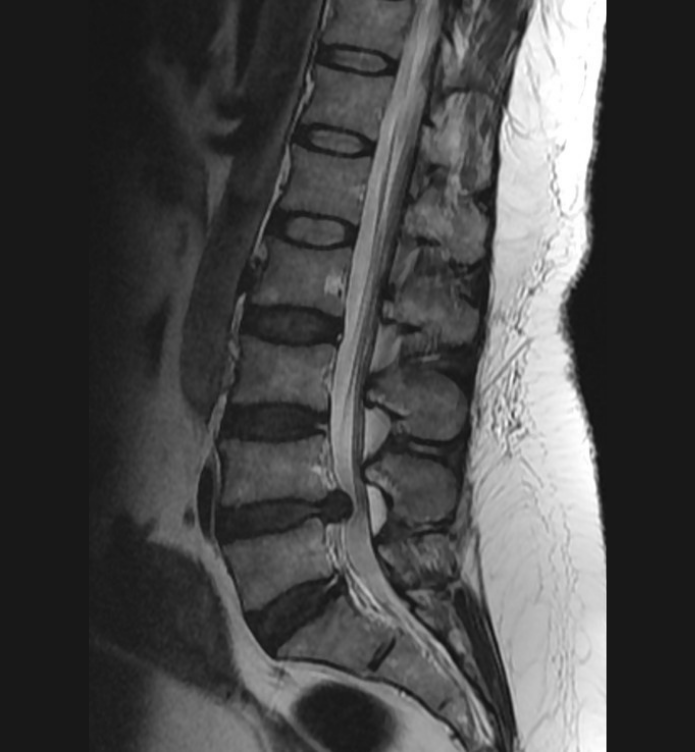

Basit Omurga ve Omurilik Anatomisi Omurga, 33 adet omur kemiğinden oluşur. Bu kemiklerin 7 tanesi boyun omuru, 12 tanesi sırt omuru, 5 tanesi bel omurudur. Beş tanesi birleşmiş olarak sakrum denilen kemiği ve 4 tanesi yine birleşmiş olarak koksiks denilen kuyruk sokumu kemiğini oluşturur. Omurganın görevi omuriliği korumak ve gövdeyi dik pozisyonda tutmak için destek […]